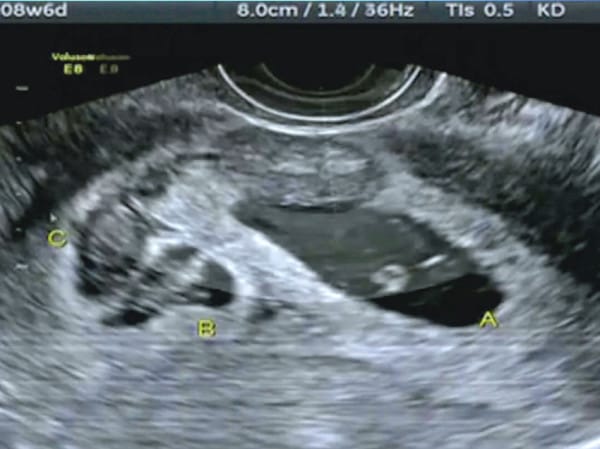

Πρόκειται για ιατρικό φαινόμενο που έχει καταγραφεί μόλις δύο φορές παγκοσμίως: Η αυστραλή Κέιτ Χιλ, που δυσκολευόταν να μείνει έγκυος, κατόρθωσε να συλλάβει δίδυμα με διαφορά… δέκα ημερών.

Οπως αναφέρει το BBC, η Κέιτ έπασχε από σύνδρομο πολυκυστικών ωοθηκών και ο γυναικολόγος της συνέστησε ορμονική θεραπεία, ώστε να επιτύχει ωορρηξία και να μείνει έγκυος. Τα αποτελέσματα της θεραπείας αποδείχθηκαν κάτι παραπάνω από ενθαρρυντικά, καθώς έμεινε έγκυος δύο φορές μέσα σε διάστημα δεκαημέρου.

Με δηλώσεις της στο αυστραλιανό Seven Network διευκρίνισε πως τα δίδυμα συνελήφθησαν σε διαφορετικές ημέρες, παρόλο που υπήρχε μόνο μία σεξουαλική επαφή με το σύζυγό της χωρίς προστασία. Μία συνεύρεση ήταν αρκετή για να γονιμοποιηθεί και δεύτερο ωάριο λίγες ημέρες μετά.

«Ο σύζυγός μου και εγώ είχαμε μόνο μία επαφή. Το σπέρμα του έμεινε ζωντανό για δέκα μέρες και κατάφερε να γονιμοποιήσει και δεύτερο ωάριο», δήλωσε η ίδια, αφού με τη βοήθεια του γυναικολόγου της κατάφεραν να διαλευκάνουν το μυστήριο.

Η Σαρλότ και η Ολίβια, τα δύο μωρά, που σήμερα έχουν ηλικία 10 μηνών, γεννήθηκαν με διαφορετικό βάρος και σωματική ανάπτυξη.

Οι περισσότερες δίδυμες εγκυμοσύνες ξεκινούν από δύο διαφορετικά ωάρια, που απελευθερώνονται όμως στις ωοθήκες προς γονιμοποίηση την ίδια ημέρα. Η περίπτωση των μονοζυγωτικών διδύμων, που προέρχονται δηλαδή από το ίδιο ωάριο, χωρισμένο εν συνεχεία στα δύο, είναι σπάνια.

Από τη στιγμή της σύλληψης και έπειτα διακόπτεται ο κύκλος της ωορρηξίας, αλλά σε εξαιρετικά σπάνιες περιπτώσεις ίσως μια γυναίκα απελευθερώσει ένα ακόμα ωάριο μετά τη σύλληψη. Αν αυτό γονιμοποιηθεί, μπορεί να εξελιχθεί σε υγιή εγκυμοσύνη. Μόλις 10 περιπτώσεις αυτού του φαινομένου έχουν καταγραφεί παγκοσμίως – η περίπτωση της Κέιτ είναι πολύ πιο σπάνια, σχεδόν μοναδική.